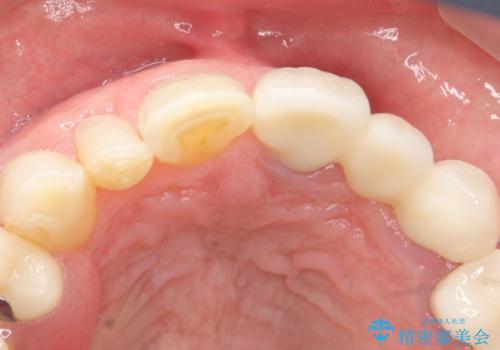

歯の牽引後、ブリッジの仮歯で保定しながら歯肉・骨の治癒を待ったのち、ブリッジによる補綴を行いました。

左上2欠損部の軟組織のボリュームが少なくポンティック部に食渣がたまりやすい歯肉形態であったため、歯槽堤増大術も提案しましたがご希望されませんでした。

ご希望により最終補綴前にホームホワイトニングを行っております。

最終補綴前に右上321の結合組織移植術(CTG)を希望されたため、大元院長に行って頂きました。